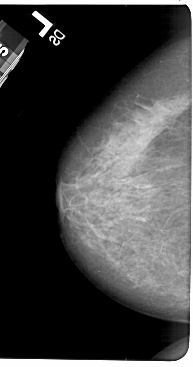

A_1602_1.LEFT_CC

LEFT_CC LINES 5491 PIXELS_PER_LINE 2881 BITS_PER_PIXEL 12 RESOLUTION 43.5 NON_OVERLAY